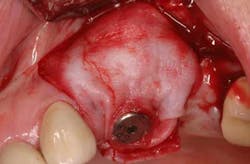

Mucograft® is an example of a xenograft material that has been used in lieu of autogenous grafts to increase keratinized tissue around dental implants (21). Made of porcine collagen, this material has a compact outer layer that can be left exposed to the oral environment and a spongy inner layer that facilitates a blood clot and promotes angiogenesis. A major advantage in using this material for increasing keratinized tissue around dental implants is that it can be used in challenging areas with little to no attached soft tissue because primary closure over this graft material is not needed and it can be left exposed (Figs. 3a-3c).

Fig. 3a: Edentulous Nos. 12 and 13 slated for implant therapy with a limited amount of keratinized tissue.

Fig. 3b: Soft tissue Mucograft placed at the time of implant surgery in order to augment keratinized tissue height and thickness. Primary closure was not obtained over this graft.

Fig. 3c: Final restorations showing a large increase in the height of keratinized tissue, facilitating oral hygiene and increasing plaque resistance.